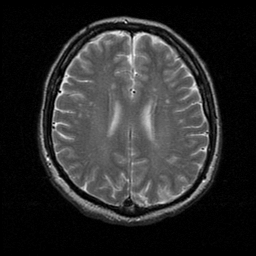

MR Study #1 -- Slice #15